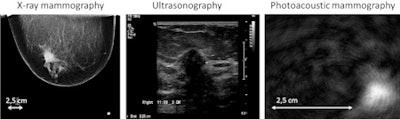

The resulting photoacoustic signals are then processed by the PAM system and reconstructed into images. These images reveal abnormal areas of high intensity that are tumor tissue as compared to areas of low intensity that are benign tissue.

By comparing the photoacoustic data with conventional diagnostic mammography images, ultrasound imaging, breast MRI, and tissue examinations, the researchers showed that malignancies produced a distinct photoacoustic signal which has the potential to be clinically useful in making a diagnosis of breast cancer. The research team also observed that the photoacoustic contrast of the malignant tissue was higher than the contrast provided by conventional mammography images.